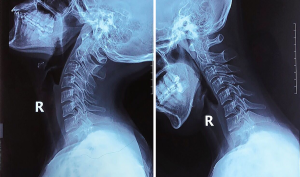

Case 3 (Figures 8 and 9 )

A 65-year-old male without significant past medical history presented to the outpatient department with a chief complaint of difficulty walking for more than 10 months’ duration, and neck and shoulder pain for 40 years. Physical examination showed bilateral upper extremity hyperreflexia, bilateral Babinski reflex, a positive Hoffman’s test, and a decrease in multidermatomal upper extremity sensation during pinprick testing. Furthermore, decreased grip strength and compromised coordination was noted, evidenced by altered gait pattern. Radiographic examination of the cervical spine showed a loss of activity in the PAOI on X-ray (ratio of PAOI = ~0.6). The MRI demonstrated the presence of severe spinal compression in C4/5. The patient elected to undergo cervical surgical treatment.